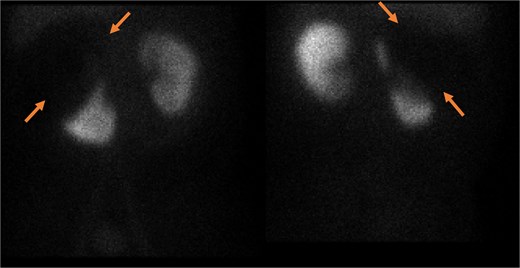

Pelvic magnetic resonance imaging (MRI) further characterized the pelvic lesion as a well-defined, non-enhancing, fluid-filled cyst measuring 3 × 2 × 1 cm without solid components, raising suspicion for pelvic hydatid seeding, although peritoneal inclusion cyst was also considered (Fig. 3). A 99mTc-dimercaptosuccinic acid (DMSA) scan showed preserved renal function with the right kidney contributing 25.7% of total function and a photopenic defect at the cyst site (Fig. 4). No other lesions were found on chest CT or brain MRI. Colonoscopy ruled out malignancy but revealed incidental low-grade adenomas.

Static image of the abdomen at 2 h after IV injection TC-99 m DMSA, showing normal morphology & corticotubular function of the left kidney. Large photopenic area occupying the upper half of the right kidney while its lower half showed preserved cortical function.